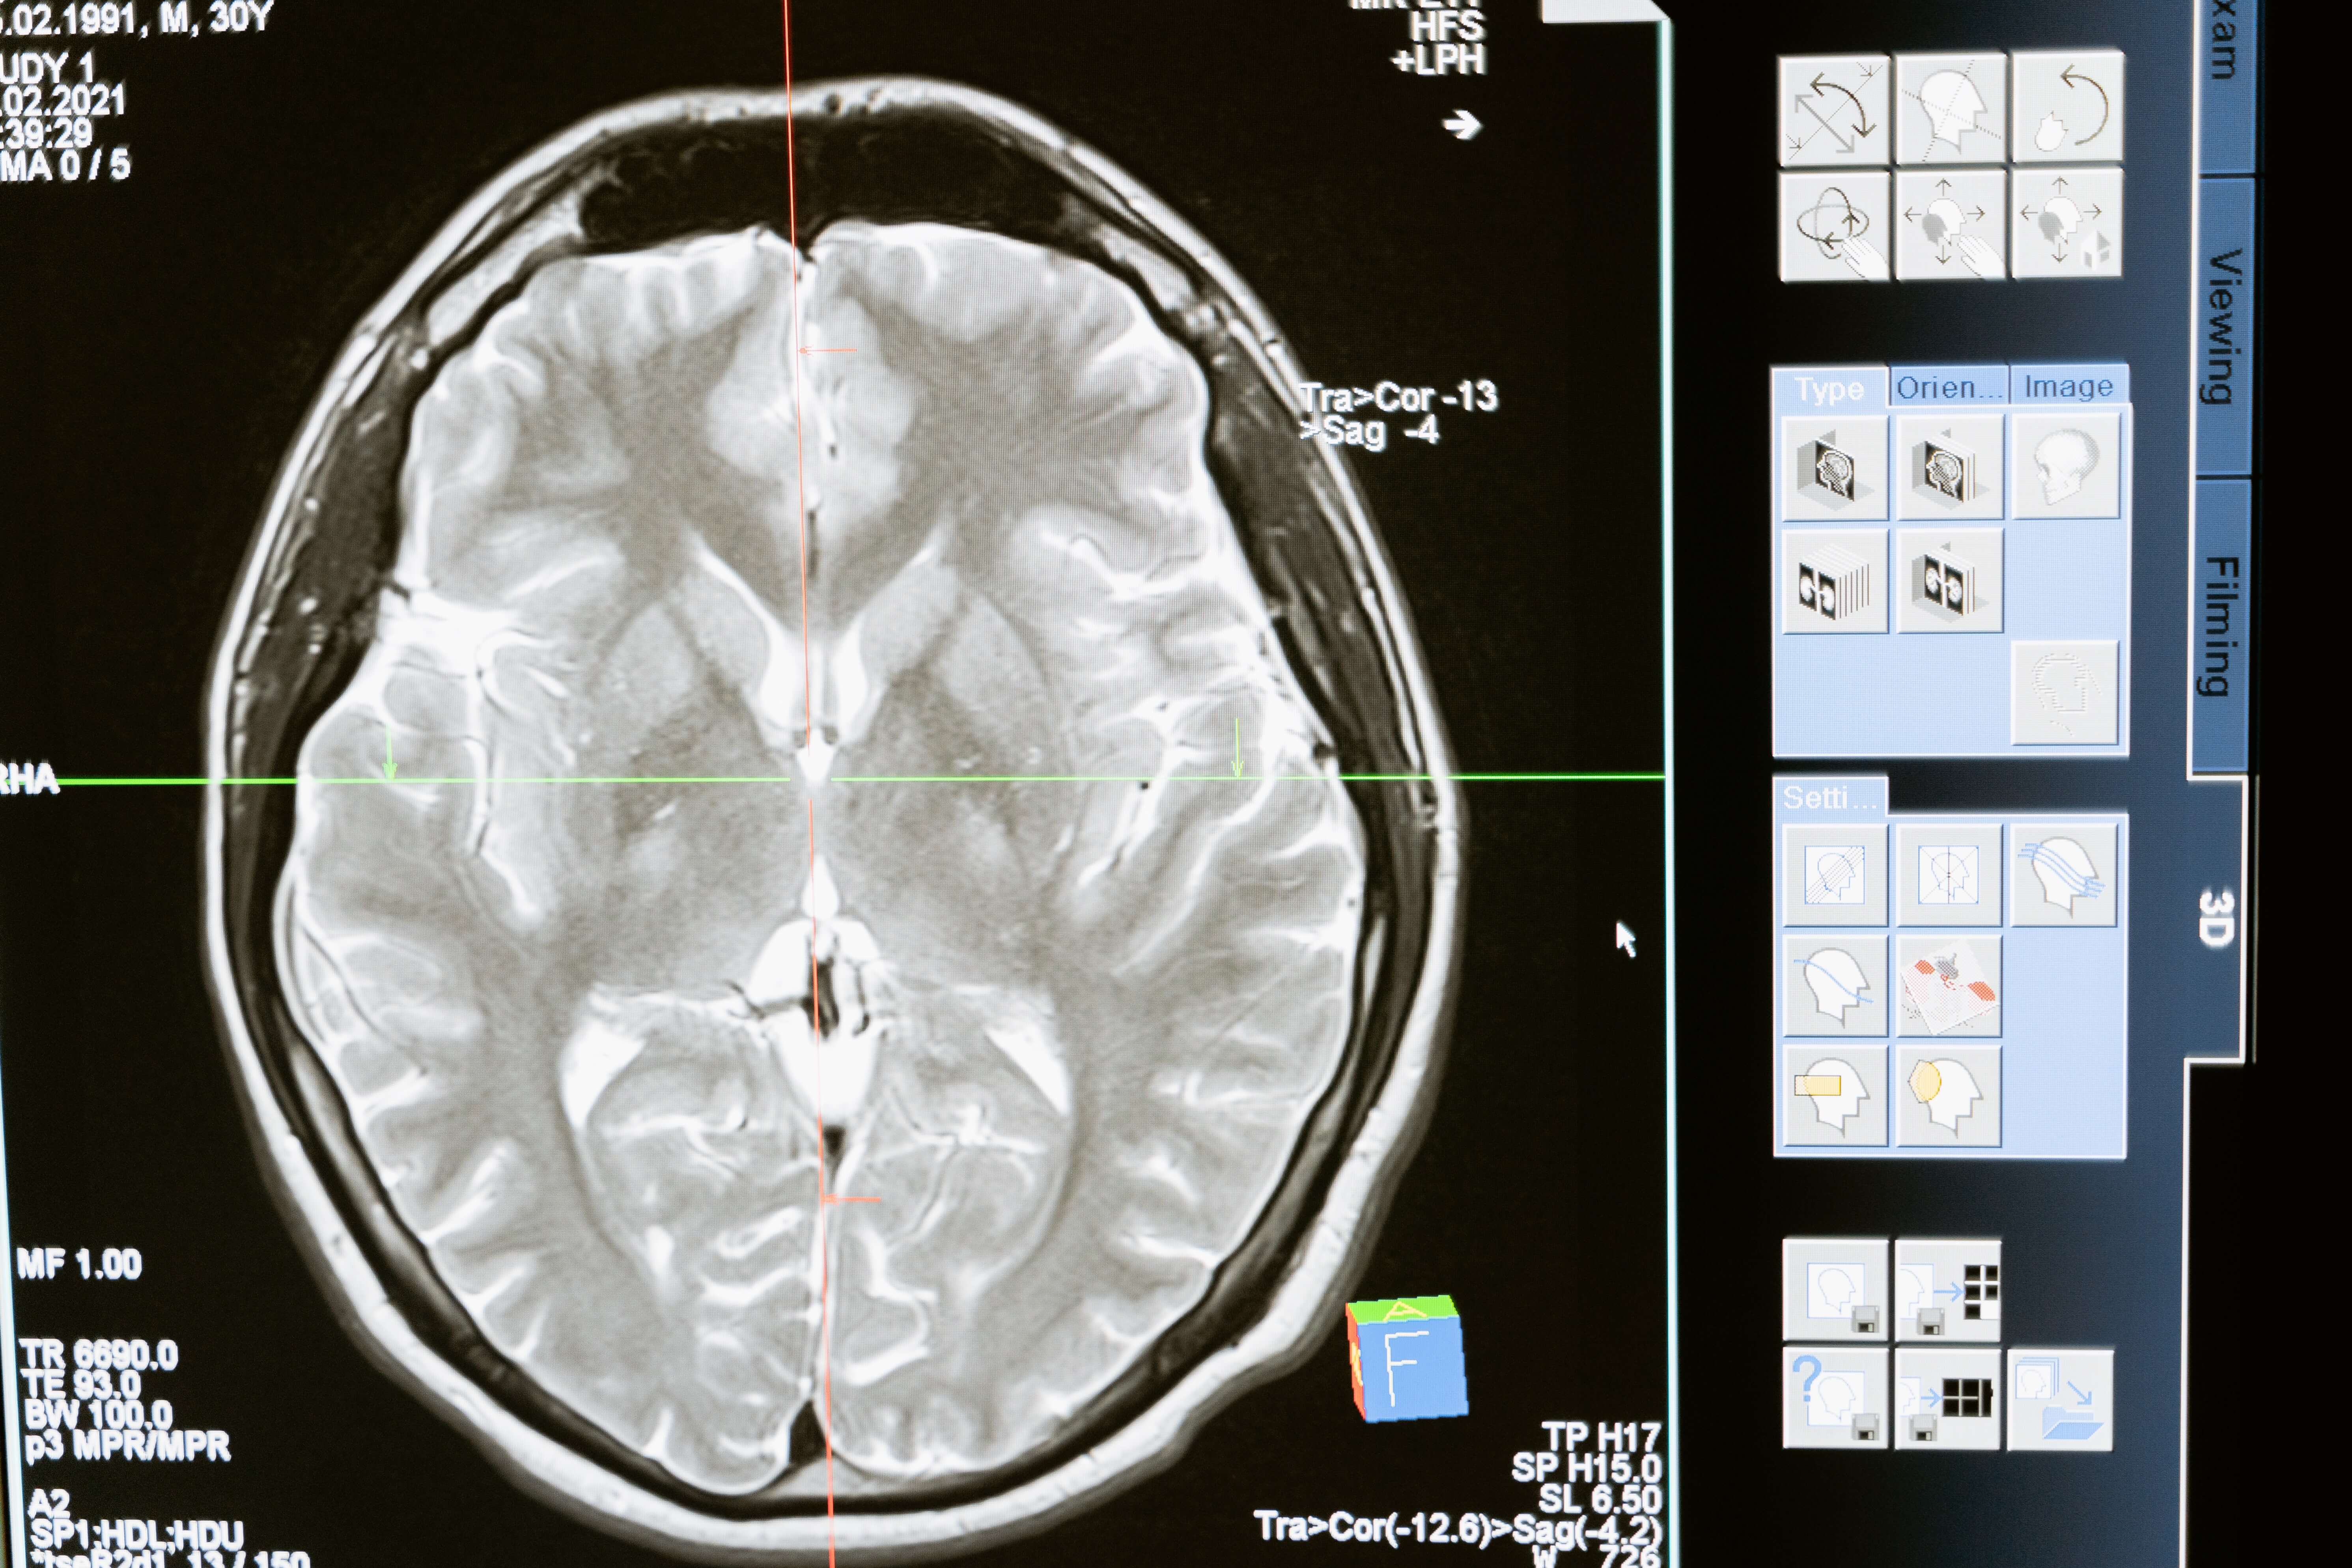

A traumatic brain injury (TBI) happens when the person experiences a jolt, blow, or bump to the head. Accidents commonly cause a TBI, resulting from falls, traffic collisions, trauma suffered while playing sports, or intentional assaults. A concussion, for example, could be a mild type of TBI, but a more severe injury to the brain might result in permanent damage. A mild form of brain injury may heal with medication and rest. Still, a moderate to severe type of trauma can cause changes in personality and emotional problems and affect the individual’s mental and physical abilities. Many people suffering from a more serious TBI must relearn even the most basic skills and require extensive rehabilitation.

A wide range of symptoms can be suffered from a TBI, which can get progressively worse, depending on the type of injury and severity. Symptoms include:

- Mild TBIs found in a concussion can include headaches, feelings of lightheadedness, ringing in the ears or blurred vision, confusion, problems concentrating and with memory, and a possible short loss of consciousness.

- Moderate to severe TBIs can cause worsening headaches, a much more extended period of unconsciousness, sleepiness, changes in pupil size, nausea, vomiting, and slurred speech. Symptoms can also include confusion, agitation, coordination problems, convulsions, seizures, and possible hallucinations.

More serious traumatic brain injuries can result in long-term disability and brain damage. The risk is also increased for the following complications: